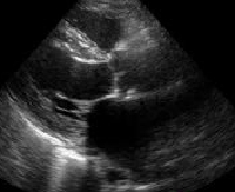

Hypertensive Hypertrophic Cardiomyopathy

Atrial Fibrillation

高血圧症、高血圧性心疾患に心房細動が併発し、

心臓の収縮能が低下した心不全状態であります。

心不全は、臨床症状、身体所見、胸部レントゲンで診断できますが、

心エコー図検査に精通すると、症状が出現する前に心不全になる可能性が

高い状態かを把握することもできます。